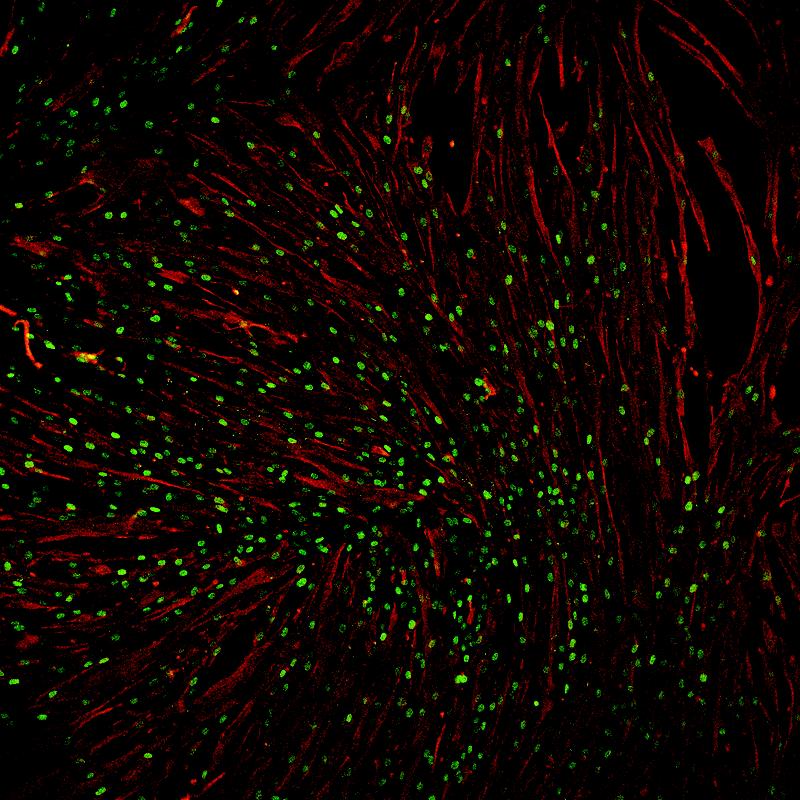

(unteres Bild)

Kultur humaner Muskelstammzellen (grün) nach vorheriger Kältebehandlung.

(Photo: Andreas Marg/ Copyright: ECRC)

Prof. Spuler und ihre Mitarbeiter kultivierten die Muskelfaserfragmente mit den Satellitenzellen zunächst für bis zu 3 Wochen. In dieser Zeit vermehrten sich die Satellitenzellen um das 20- bis 50fache, aber auch zahlreiche Bindegewebszellen entwickelten sich in diesen Kulturen. Um das zu verhindern, unterzogen sie die Muskelfragmente gleichzeitig einem Sauerstoffentzug (Hypoxie) und einer Kühlung (Hypothermie) bei 4 Grad Celsius. Unter diesen Bedingungen können nur Satellitenzellen in ihrer Stammzellnische überleben, nicht aber die Bindegewebszellen. „Offenbar erhalten die Satellitenzellen im eigenen ,Hausʽ die notwendige Versorgung“, so Dr. Marg.

Erstmals ist es den ECRC-Forschern mit ihren Versuchen gelungen zu zeigen, dass es möglich ist, Satellitenzellen des Menschen zu kultivieren, zu vermehren und ihr Regenerationspotential für einige Wochen zu erhalten. Damit haben sie eine wichtige Voraussetzung für die Nutzung patienteneigener Zellen für die Therapie geschaffen.